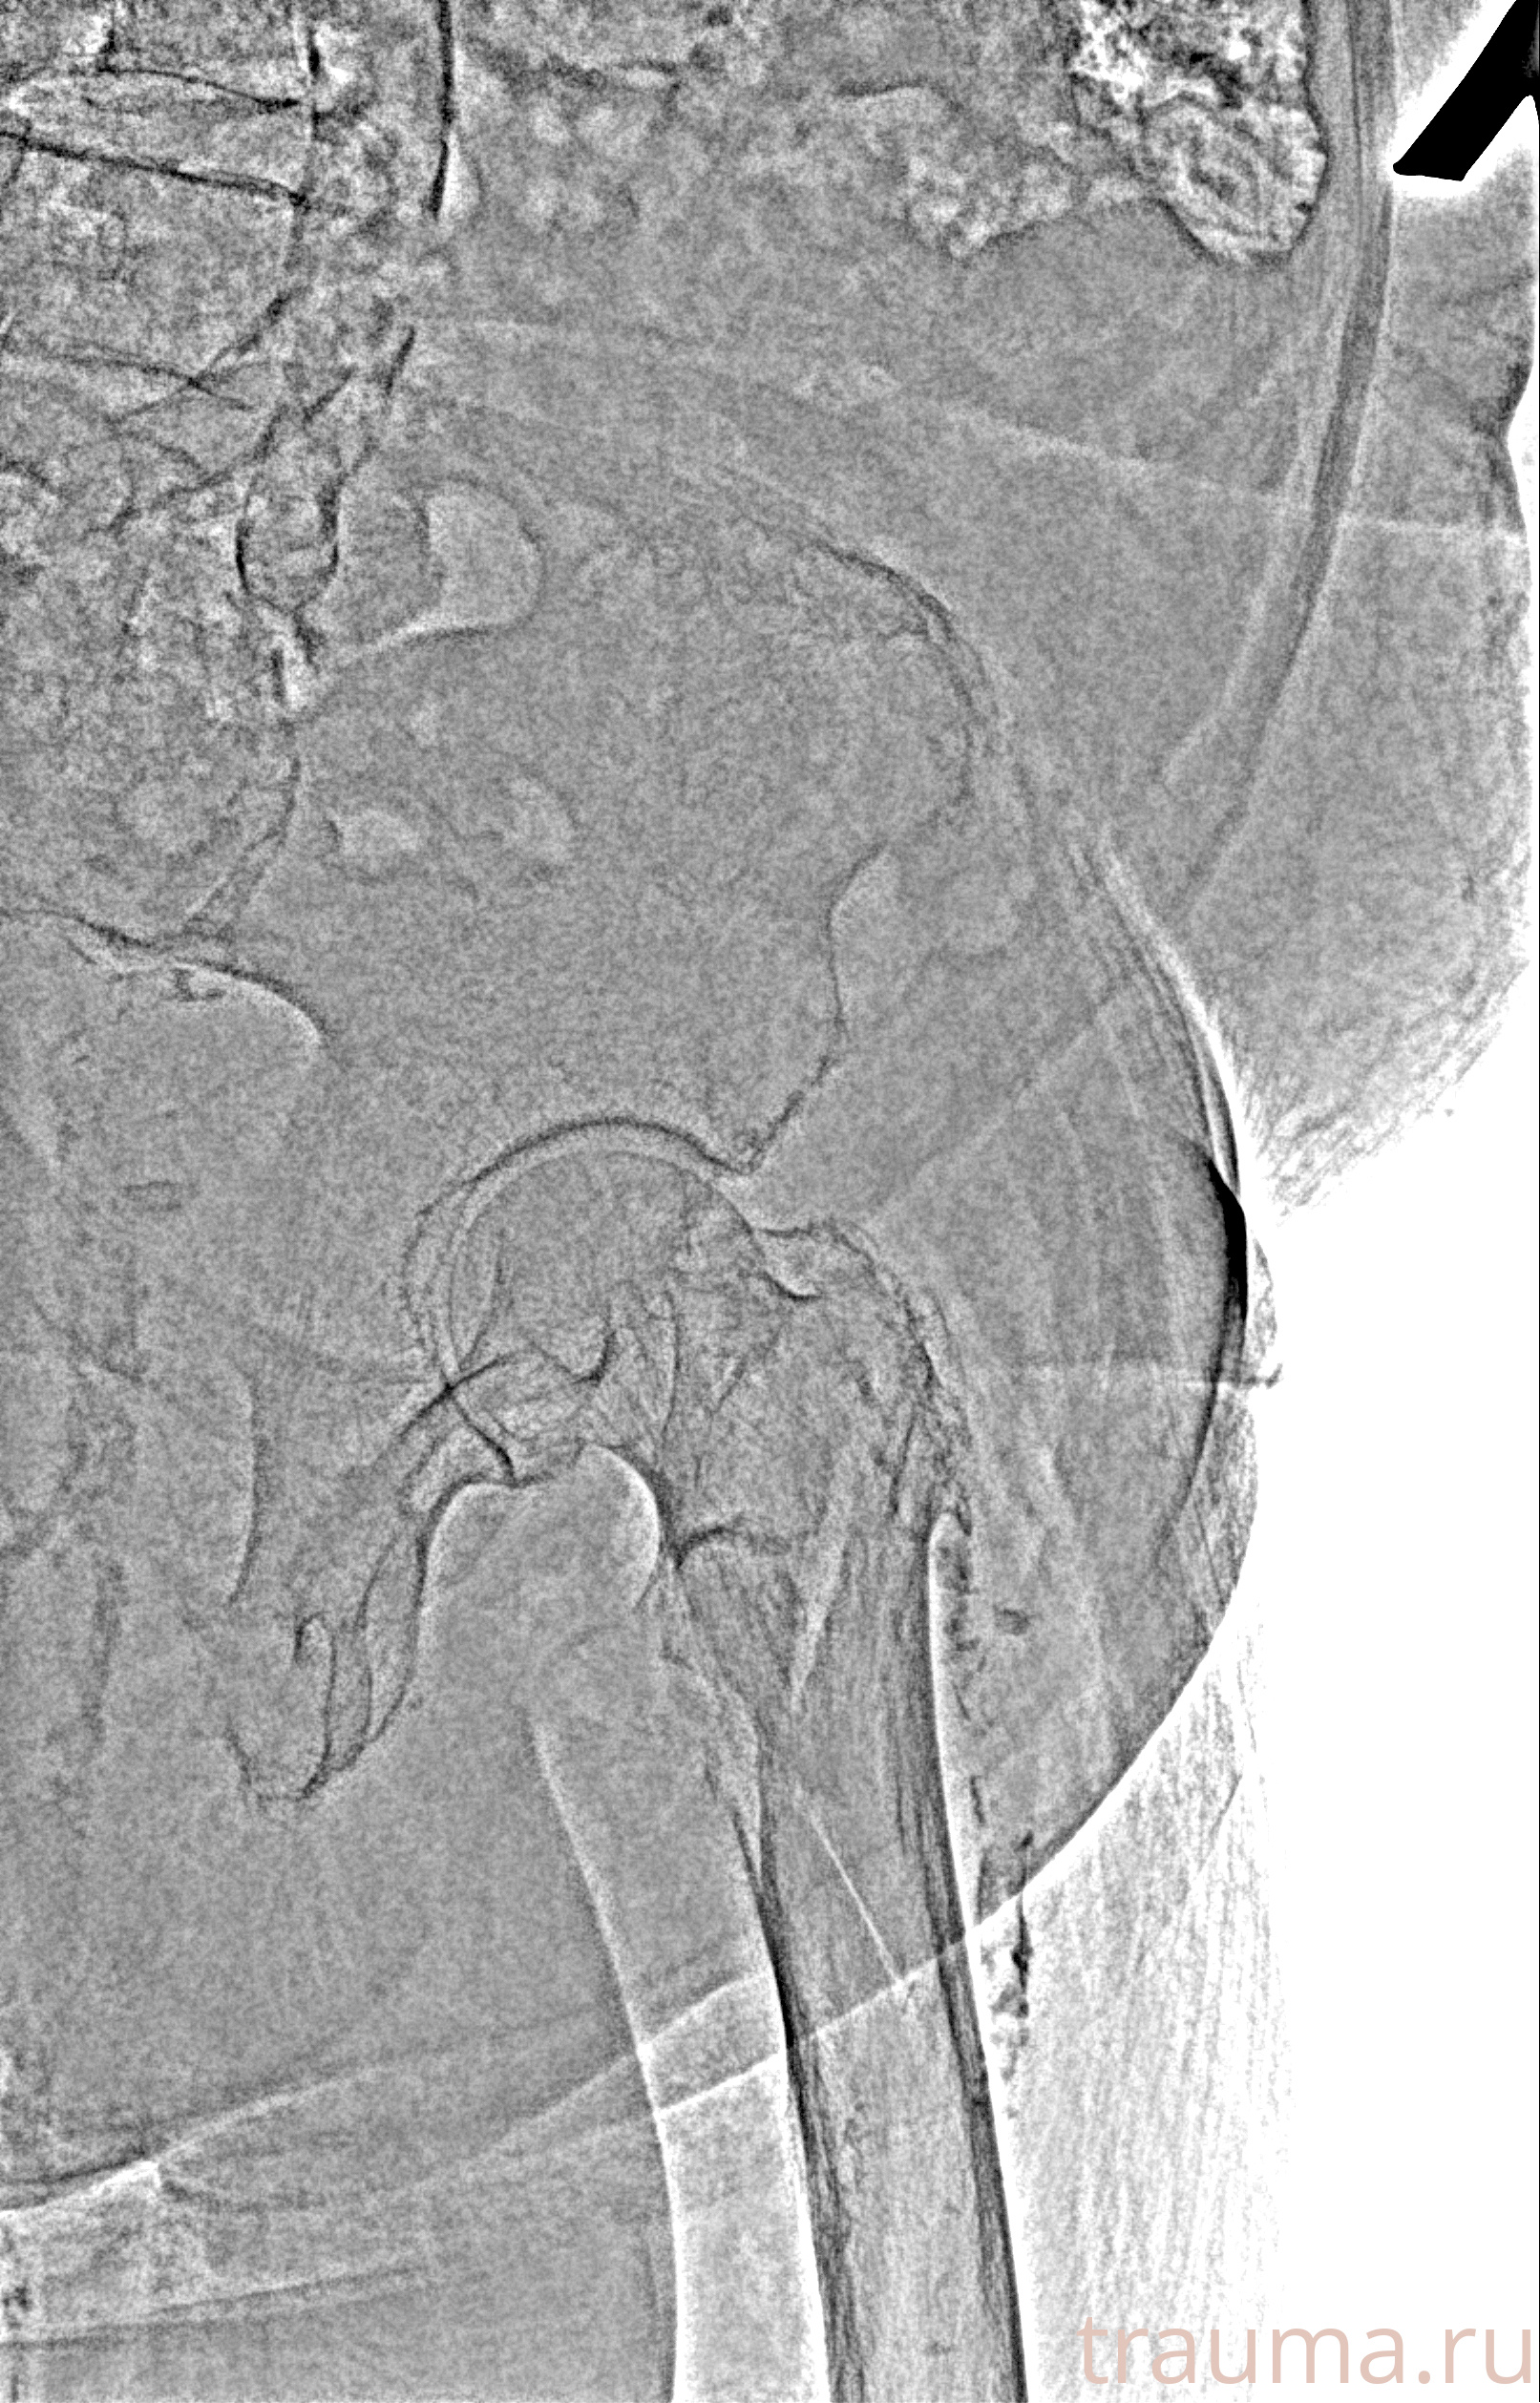

Рентгенограммы

Рентген на дому: по вашему адресу приезжает врач-рентгенолог, травматолог-ортопед с мобильным рентгеновским аппаратом, проводит диагностику травмы или заболевания, делает необходимые рентгенограммы, дает рекомендации по дальнейшему лечению. Получить качественные снимки в домашних условиях возможно благодаря уникальной методике, разработанной МосРентген Центром для института  Склифосовского

Яркость: 1   Контраст: 1   Инвертировать: 0 Увеличение: 1

Перетаскивайте мышь вверх/вниз для контраста, влево/право для яркости. Прокрутка колесом изменяет масштаб. Нажмите Сбросить для возврата к исходному изображению. При увеличении держите мышь в той области, которую хотите рассмотреть.